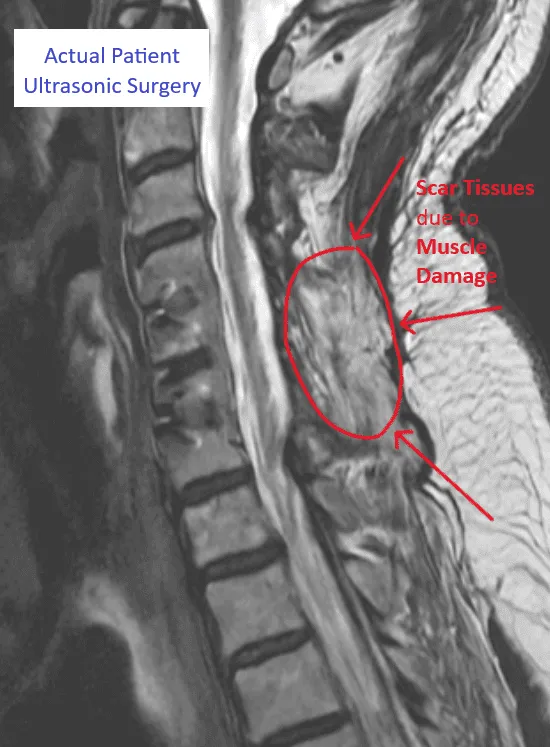

MRI showing spinal structure with labeled scar tissue from muscle damage.

Muscle Damage

Close-up of lung tissue showing bronchioles in pink and red hues.

Scar Tissue Formation